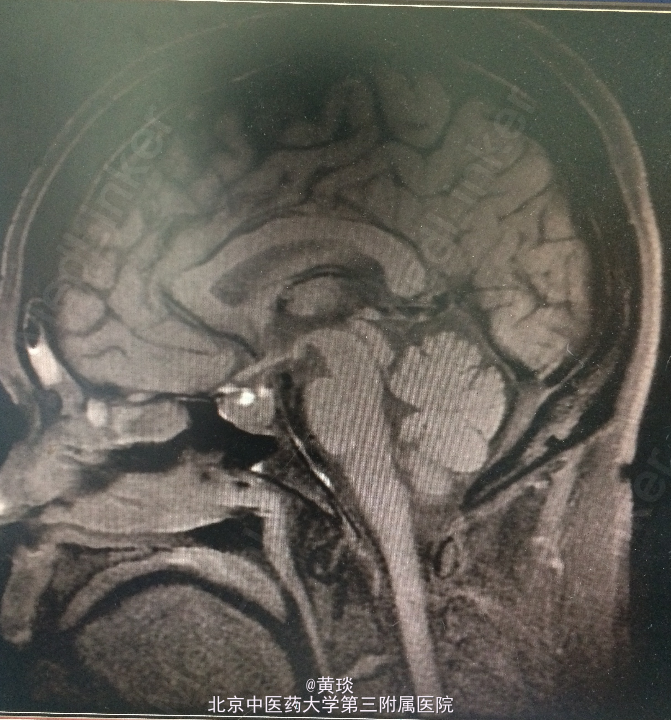

患者女,49岁,主诉:间断头痛2年,视物模糊1年。 现病史:患者2年前无明显诱因出现头痛,为前额钝痛,症状间断出现,发作时无恶心呕吐、无肢体抽搐、无肢体无力及大小便障碍、无意识障碍,未进行系统诊治。一年前起患者自觉视物模糊,偶伴有发热及烦躁不安,无面部感觉异常及眼球活动受限,无闭经泌乳、无多饮及多尿,右耳偶有耳鸣,无听力下降,无发作性头晕及走路不稳,无饮水呛咳及声音嘶哑,门诊行头部MRI检查,提示鞍上异常信号影。以“鞍区占位”收入院。

查体:双侧瞳孔等大等圆,直径约2mm,对光反射灵敏,左侧视力0.5,右侧视力0.6。其余无异常。 门诊头部MRI:提示鞍上异常信号影。

诊断:鞍区占位 处理:全麻下行经鼻蝶鞍区占位切除术

术前考虑的诊断:1.垂体瘤:为鞍区最常见肿瘤,患者可伴或不伴内分泌症状,临床可表现为视力视野受损或内分泌改变如多饮多尿等,影像学检查可见鞍区占位性病变,依据患者症状体征及辅助检查,诊断可能性大,具体待术后病理。 2.鞍区脑膜瘤:为鞍区常见肿瘤,多分布于蛛网膜颗粒聚集处,边界清楚,均匀强化,有时可见脑膜尾征,临床可表现为颅内占位效应,如视力下降等,依据患者症状体征及辅助检查,该诊断不能排除,具体待术后病理。 3.鞍区动脉瘤:较少见,但手术风险大,临床表现为视力改变,影像学见占位边界清楚,MRI见血管流空影,该诊断可能性小,但不能排除。 4.颅咽管瘤:多发于鞍区,儿童多见,临床可表现为视力下降或内分泌改变,影像学检查就CT可见蛋壳样钙化,该诊断基本可排除。 术后病理确诊为垂体瘤。